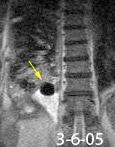

Marzo 2014: Perforación longitudinal distal secundaria a episodio de vómito (síndrome de Boerhaave). Derrame pleural izdo. que evoluciona a empiema.